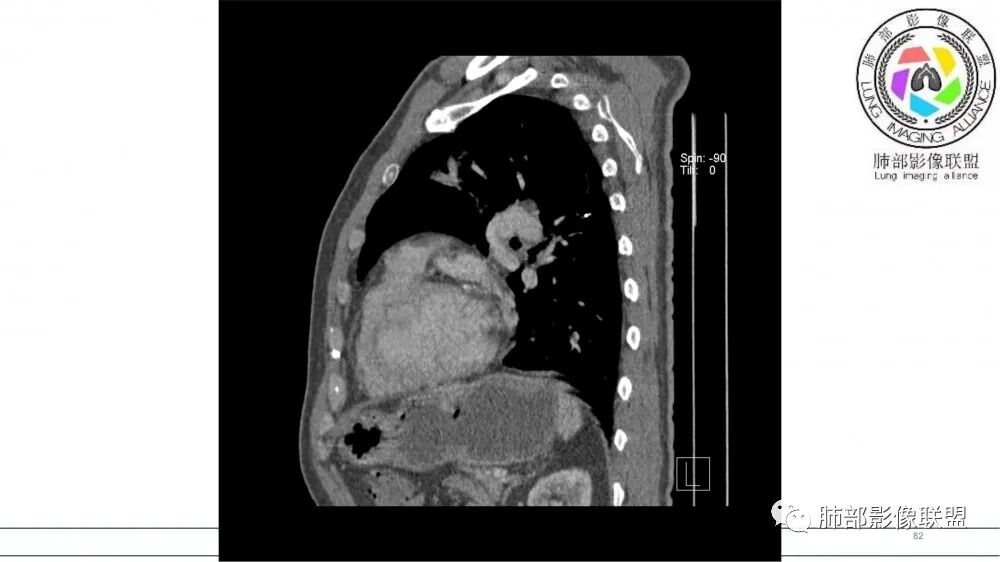

2021年8月6日晨读病例结果:小细胞肺癌

资料拓展-指套征

指套征:是影像征象,胸部平片表现为手指状密度增高影,以肺门为中心呈放射状分布,CT显示扩张支气管内低密度黏液栓形成或实性病变,呈管状、树枝状或卵圆形密度增高影;支气管扩张伴近端梗阻时,扩张支气管内部黏液分泌物不能排出而形成。可以伴随远端空气潴留征、阻塞性炎症。

研究报道,中心型 SCLC 经 CT 扫描后通常支气管表现为鼠尾样狭窄,肺门或纵隔肿块明显,由于肿块沿管壁生长表现为顺延支气管形态的不规则形状。病灶相对特征性影像学表现比如鸭蹼状、腊肠状、葫芦状及葡萄状改变,可以出现血管包埋,很少有空洞、空泡,较少引发肺不张,阻塞性炎症成都较轻。与一般肺癌比较,恶性程度高,侵袭力强、病灶很小就容易远处转移!Herzberg 等[19]研究指出,20%以上 SCLC 倍增时间短,预后不良。